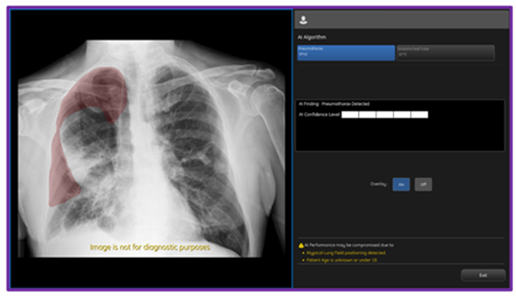

CHICAGO--(BUSINESS WIRE)--Today GE HealthCare (Nasdaq: GEHC) announced an industry-first US FDA 510K clearance of Critical Care Suite 2.1 featuring a Pneumothorax (PTX) algorithm for the detection, notification, triage and diagnosis of PTX. The updated PTX algorithm expands Critical Care Suite’s on-device triage capabilities by providing immediate notification of the presence or absence of pneumothorax, as well as an overlay display both on-device and in PACS to assist with PTX localization.

With this latest update, Critical Care Suite 2.1 provides immediate on-device detection and triage notifications for the presence or absence of pneumothorax (PTX). When a PTX is detected, an overlay is displayed in the area where the PTX was located both on-device as well as in PACS to assist with PTX localization, as well as improve speed and accuracy of PTX diagnosis. By hosting Critical Care Suite on-device, critical insights are available at the point of care and across the entire clinical care team.

The algorithm operates with a high degree of accuracy – partially localizing 100% of all detected large PTXs and 96% of all detected small PTXs, while limiting false alerts (94% specificity).7